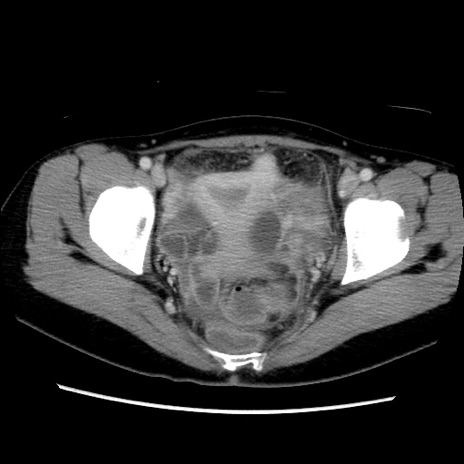

症例39(横断像)

【症例】40歳代女性

【主訴】上下腹部痛

【現病歴】2日目から下腹部痛あり。夜間は痛みで眠れなかった。昨日より上腹部痛と下痢が出現。臥位で痛みは軽快したため、休んでいた。本日になって臥位でも立位でも痛みが強くなってきたため救急要請。

【既往歴】子宮内膜症

【身体所見】部:平坦・軟、左上下腹部に圧痛あり、反跳痛あり。

【データ】WBC 21800、CRP 26.78